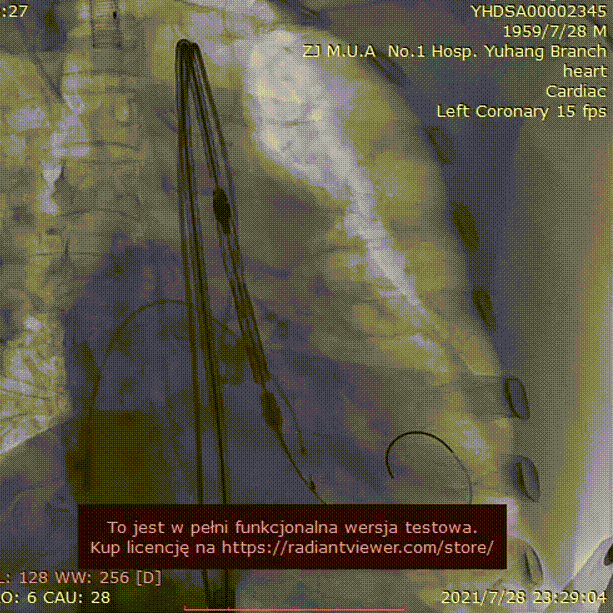

手术过程:

20mm球囊预扩

(无腰征,少量瓣周漏)

TAV24 瓣膜释放前定位

释放过程

植入后造影

术后压差1mmHg

术后结果:测左室-主动脉平均跨瓣压差3mmHg。

术中经食道心超评估: